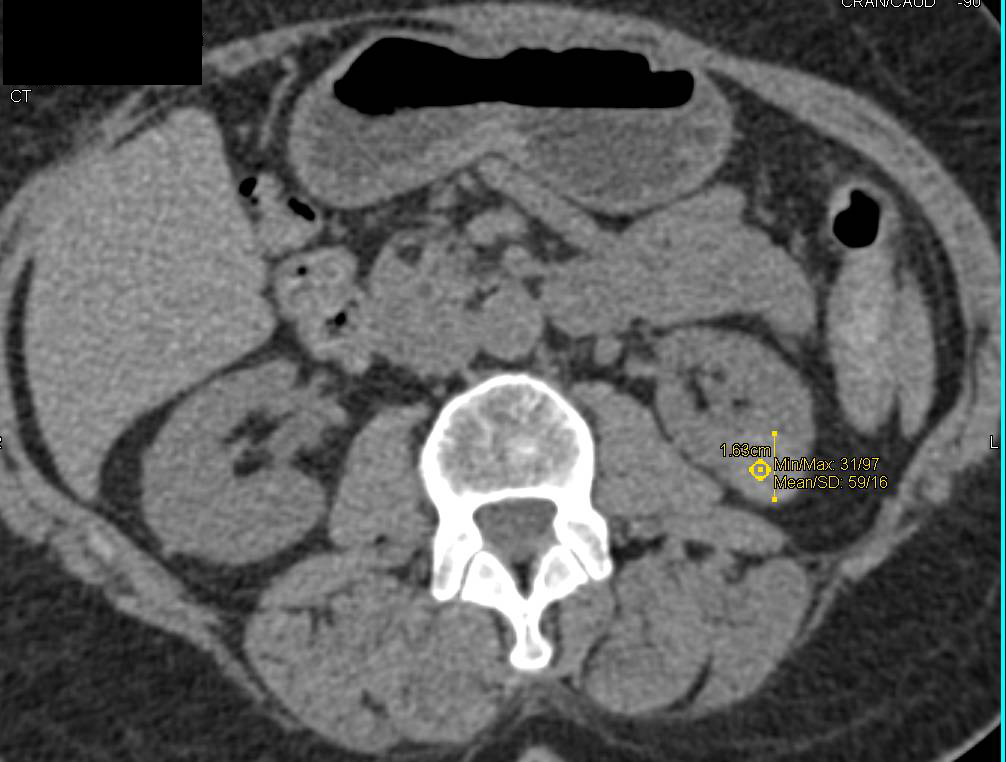

High Density Renal Cyst with Multiple Phases and Displays